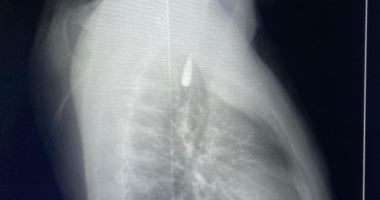

وأوضح الدكتور تامر عبد الله، عميد كلية الطب ورئيس مجلس إدارة المستشفيات الجامعية، أنه في يوم 21 أكتوبر 2025 تمكن فريق من أطباء قسم جراحة القلب والصدر والتخدير والمعاونين من إجراء جراحة دقيقة بالغة الخطورة لأحد المرضى المحجوزين من قطاع غزة، والذي كان قد تعرض لإصابة بطلق ناري في الرأس منذ فترة، استقر المقذوف على إثرها داخل تجويف القفص الصدري قرب الشريان الأورطي، وهو أكبر وأهم شرايين الجسم والمسؤول عن تغذية جميع الأعضاء الحيوية، وأضاف أن الفريق الطبي، رغم دقة الحالة وتعقيدها، نجح في استخراج المقذوف بأمان بعد عملية جراحية نادرة استمرت عدة ساعات داخل المستشفى الجامعي الجديد، حيث خضع المريض بعدها للرعاية الطبية اللازمة، وحالته حاليًا مستقرة وتحت المتابعة الدقيقة من الفريق المختص.